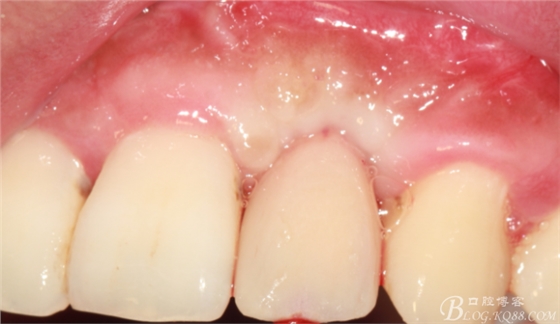

兩個(gè)月后戴入永久修復(fù)體。

戴入永久修復(fù)體當(dāng)天口內(nèi)照,雖有小瑕疵,但患者很滿意。